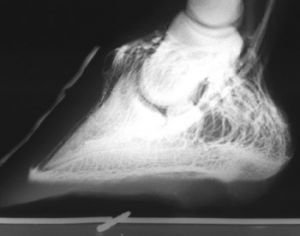

Krev je do kopyta přiváděna párem prstních tepen, které prostupují pod kopytní kladkou a vstupují do kopytní kosti a vytváří uvnitř kopytní kosti terminální oblouk. Z prstních artérií vystupuje několik větví ještě před vstupem do kopytní kosti a spousta větví uvnitř kopytní kosti zásobujících lamelární kopytní škáru. Zásobují také obvodovou tepénku vedoucí po okraji kopytní kosti, z níž vystupují větve prokrvující chodidlovou škáru. Tepénky se hustě rozvětvují v kopytní škáře, vytváří velké množství anastomóz a protkávají kopytní škáru velmi hustou sítí vlásečnic. Vlásečnice přecházejí do žilního systému, který je opět velmi hustý, rozvětvený s řadou anastomóz. Žíly se spojují ve větších žilních cévách a v korunce tvoří hustou žilní síť. Z korunkové žilní sítě pak odchází opět dvě prstní žíly stoupající vzhůru k srdci, které zesilují a uvnitř vytváří řadu chlopní, které zabraňují zpětnému toku krve.

Spleť cév v kopytní škáře (lístkové a chodidlové) se naplňuje krví přitékající prstními tepnami.

Rohové kopytní pouzdro se vrací do původní polohy stejně jako kopytní kost. Krev ze škáry je tímto smrštěním vytlačena do korunkové žilní spleti.

Krev nacházející se v korunkové žilní spleti je poklesem korunky a tlakem rohového pouzdra na korunku vytlačena do prstních žil a odtéká směrem k srdci.